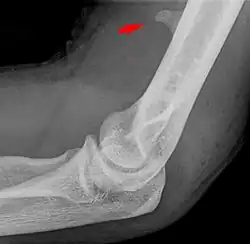

Le processus supracondylaire de l’humérus (ou apophyse sus-épitrochléenne) (en latin : processus supracondylaris, en anglais : supra-condyloid process ou supra-trochlear spur) est une petite formation osseuse situé sur l'humérus, rare chez l'espèce humaine. Elle a été décrite pour la première fois par Friedrich Tiedemann en 1822[1]. Elle correspond à une formation analogue présente de façon constante chez certains mammifères.

L’apophyse sus-épitrochléenne possède une forme approximativement pyramidale, elle est située à environ 6 cm (chez l’adulte) au-dessus de l’épitrochlée et à mi-distance des bords interne et antérieur de l’humérus[2]. La plupart du temps, une bandelette fibreuse fait suite à l’apophyse et forme avec elle un canal ostéofibreux où passe le nerf médian accompagné en général d’une artère[3].